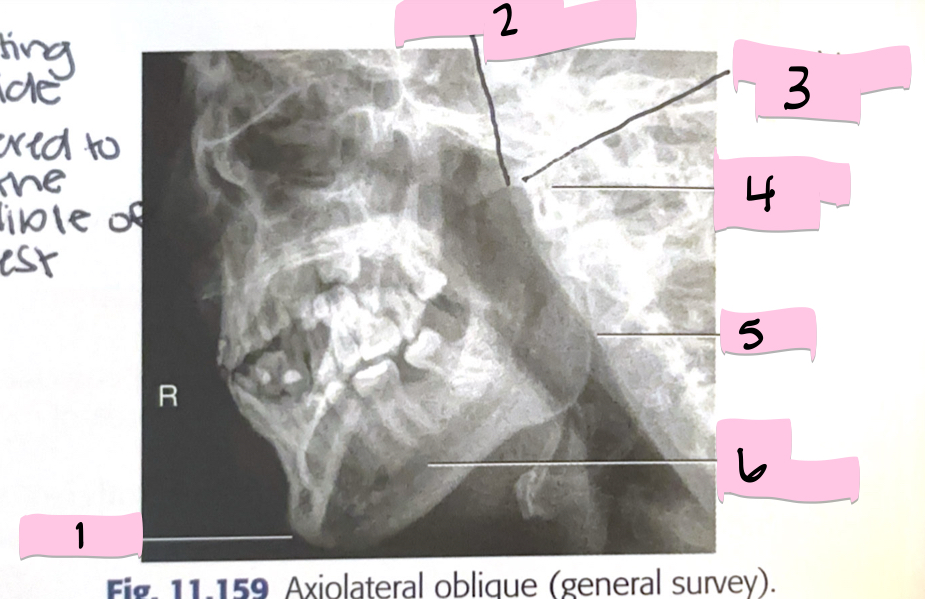

What is 1 pointing to?

Frontal sinus

What is 2 pointing to?

Superior orbital fissure

What is 3 pointing to?

Bony nasal septum

What is 4 pointing to?

Anterior nasal spine

What is 5 pointing to?

Crista galli

What is 6 pointing to?

Petrous ridge

What is 7 pointing to?

Floor of orbit

What is 8 pointing to?

Maxillary sinus